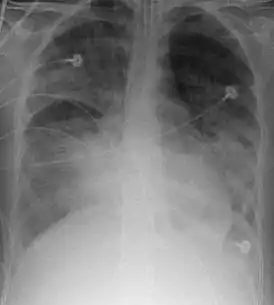

![]() Рентгенограмма органов грудной клетки пациента с ОРДС | |

При рентгенографии лёгких видны двусторонние диффузные инфильтраты, иногда — плевральный выпот. Такие признаки неспецифичны и также характерны для кардиогенного отёка лёгких, что затрудняет дифференциальную диагностику[15][16]. Компьютерная томография показывает негомогенную инфильтрацию лёгких в определённых отделах (в задненижних отделах у лежачих больных)[17]. Это объясняется зависимым от силы тяжести распределением отёка лёгких и сдавлением вышележащими отёчными отделами лёгких[18].